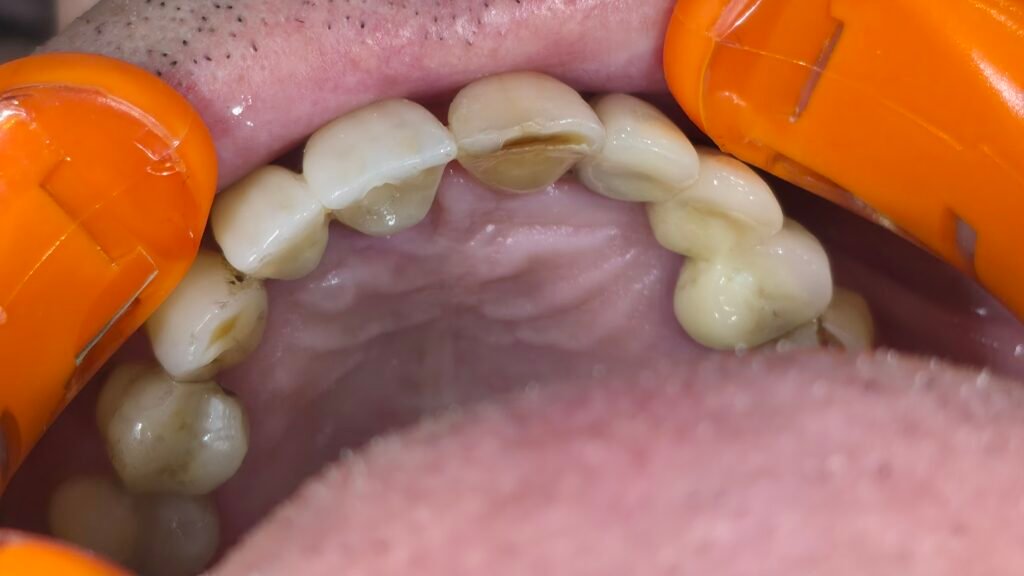

Réhabilitation complète mandibulaire : 4 implants et mise en charge immédiate

Patiente présentant une édentation mandibulaire nécessitant une réhabilitation complète implanto-portée.

Le plan de traitement a consisté en la pose de 4 implants au niveau de la mâchoire inférieure avec mise en charge immédiate, permettant une restauration fonctionnelle et esthétique rapide.

La réhabilitation finale a été réalisée par un bridge complet vissé, garantissant stabilité, confort et maintenance facilitée.